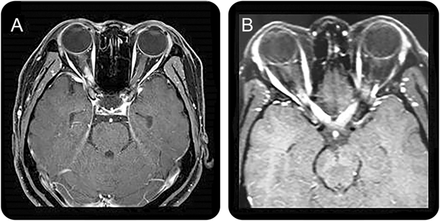

间脑的第三脑室和脑导水管周围的病变,包括丘脑、下丘脑、中脑的前边缘在NMOSD已报告(图1一个)。10,12这些病变通常无症状,但有些病人可能有抗利尿激素分泌不当综合征,e6嗜睡症,e7体温降低,低血压,嗜睡,肥胖,e8甲状腺功能减退、高泌乳素血症、继发性闭经、乳溢和行为变化。e9

间脑的病变周围(一)第三脑室和脑导水管,(A.b),包括丘脑、下丘脑、中脑的前边缘(交流)。(本科)背脑干损伤邻近第四脑室,(反方向)线性髓病变与颈脊髓损伤,相邻(公元前)水肿和大量的背侧脑干病变涉及小脑脚。(一个)立即胼胝体病变侧脑室,室管膜衬后,(C.b)“大理石模式”胼胝体的病变,(运费到付)“拱桥模式”胼胝体的病变。块状半球白质病变,簇状(地方检察官)(D.b)长spindle-like或放射状病变白质束后,(特区)广泛和汇合的半球病变显示表观扩散系数地图上增加扩散系数表明vasogenic水肿,(d)在慢性阶段半球病变显示cystic-like腔的变化。(E.a)皮质脊髓束损伤涉及的内囊后肢和中脑(后代e.b.)大脑脚(欧共体)纵向锥体束后广泛的病变。(范围内)的云雾状增强(F.b)侧脑室的室管膜表面的线性增强,(F.c)脑膜增强。